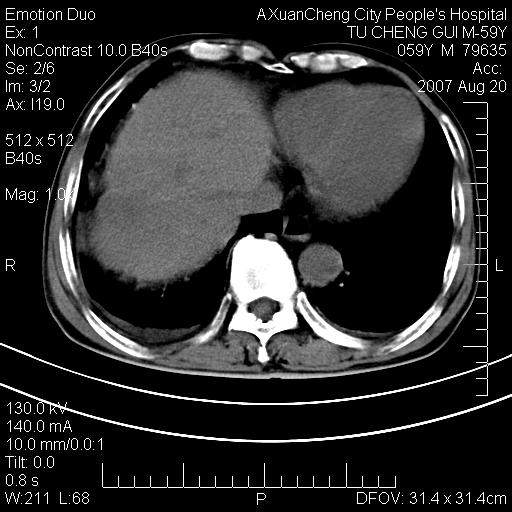

标题: CT9451:M59Y,肝脏占位

肝区涨痛一周,肝功能转氨酶均轻度增高

巨块性肝癌!(平扫不均匀低密度,增强方式典型的快进快出)

患者有肝硬化,平扫病灶呈不均性低密度,增强呈快尽快出表现,内见更低密度灶,静脉期延迟期呈低密度符合肝癌表现,内低密度为坏死改变并少量胸腹水。